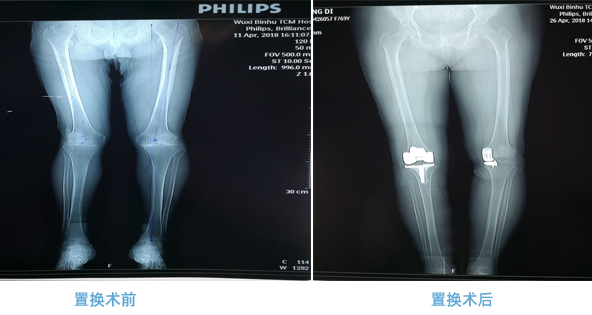

全膝人工关节置换术(total knee arthroplasty,TKA)是目前治疗膝关节退行性关节炎的常规治疗手段。术后可有效缓解膝关节疼痛、矫正畸形、改善膝关节的运动功能,被认为是目前治疗膝关节骨性关节炎最有效的方法。

幸运轮盘娱乐中心 骨伤科关节置换手术案例术前术后对比图